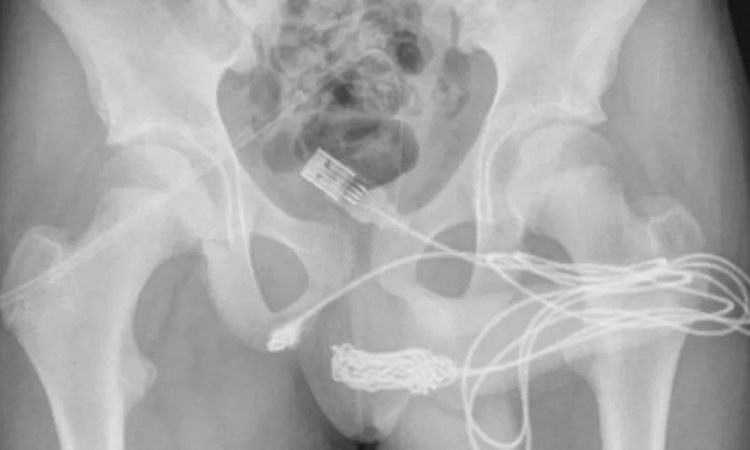

Um caso inusitado, que aconteceu no Reino Unido em 2021, ganhou destaque novamente. Um menino de 15 anos ficou com um cabo USB preso dentro do pênis após uma brincadeira sexual, informou o jornal britânico Daily Star.

O que era para se uma diversão acabou parando no hospital, pois ele precisou ir para sala de emergência remover o objeto. O equipamento não só tinha ficado preso, como fez alguns nós e ficou enrolado na uretra.

Segundo os médicos que realizaram a operação, “o paciente era um adolescente saudável e em boa forma, sem histórico de distúrbio de saúde mental. As duas pontas do fio USB estavam saindo do meato uretral externo, enquanto a parte do meio do fio permanecia dentro da uretra”, informaram.

Não foi fácil retirar o cabo, foram duas tentativas até que o procedimento fosse bem-sucedido. “Foi feita uma incisão peno-escrotal longitudinal sobre o corpo e uma dissecção cuidadosa dos tecidos mais profundos, seccionando o músculo bulboesponjoso. Ambas as extremidades do fio foram puxadas com sucesso através do meato uretral”, explicaram os especialistas.